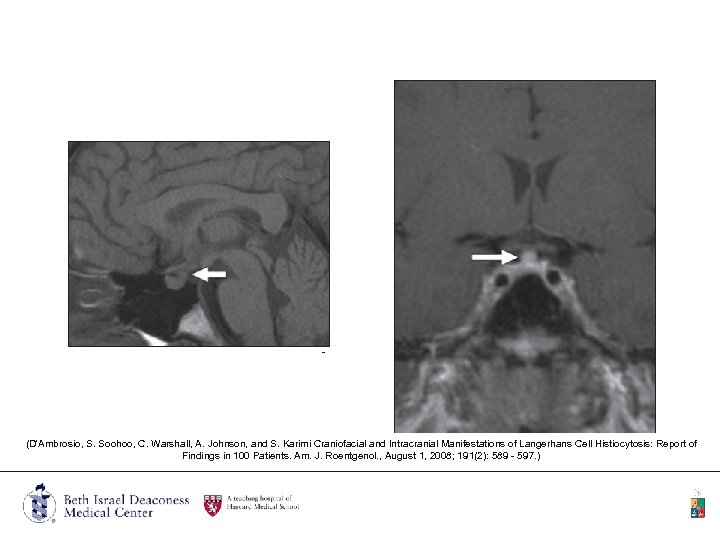

CNS • The most common CNS locations involved are the hypothalamic–pituitary axis and cerebellum. • Diabetes insipidus is the most common endocrine manifestation of LCH. • MRI findings in central diabetes insipidus are characterized by lack of high signal intensity of the posterior pituitary on T 1 weighted images, which is often associated with enhancement and thickening of the pituitary stalk.

(D'Ambrosio, S. Soohoo, C. Warshall, A. Johnson, and S. Karimi Craniofacial and Intracranial Manifestations of Langerhans Cell Histiocytosis: Report of Findings in 100 Patients. Am. J. Roentgenol. , August 1, 2008; 191(2): 589 - 597. )

Skull • In the calvarium, the lesions are round or oval lytic lesions, and have a characteristic beveled edges. (D'Ambrosio, S. Soohoo, C. Warshall, A. Johnson, and S. Karimi Craniofacial and Intracranial Manifestations of Langerhans Cell Histiocytosis: Report of Findings in 100 Patients. Am. J. Roentgenol. , August 1, 2008; 191(2): 589 - 597. )